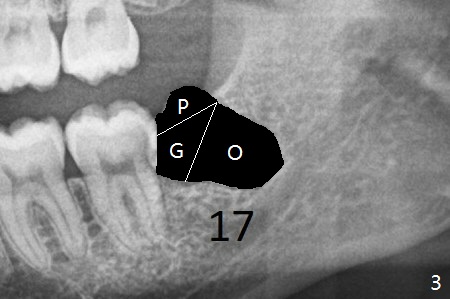

A 28-year-old woman returns for #17 and 32 extraction. To obtain full potential of bone regeneration after extraction, 3 D Bond (Graft Binder Cement, .5 cc, Fig.2 C) will be placed in the root portion of the socket of #32 , while allograft (G) and Collagen Plug (P) in the coronal one. For comparison, Osteogen Plug (Fig.3 O) will be inserted in the root portion of the socket of #17, while the other two materials same as those at #32. Take postop panoramic bitewing if both teeth are extracted. Otherwise take PA. Place the latter in the center of the extraction socket.

In fact the tooth #32 is extracted first; the defect involves the distobuccal aspect of the tooth #31 (Fig.4 *). An intraop PA is taken after extraction to confirm whether a broken surgical fissure bur tip retains or not; the distal lamina dura of #31 is low (Fig.5 *). It is expected to increase after cocktail bone graft (Fig.5' arrow). As planned, the bone cement (Fig.6 C) and allograft (G) are placed in the distal and mesial portions of the socket; between them is Osteogen Plug (O). Another piece of Osteogen Plug (as collagen membrane for bone graft) is placed on the top of the socket before suturing with 4-0 Plain Gut (Fig.7,7' O). Also note the bone graft being placed distobuccal (CT study) to #31 (Fig.7' red dashed line) to reduce possibility of future periodontitis. The patient returns 15 days postop with chief complaint of mild pain since extraction, although the wound looks normal. The transverse cortex connecting to the lamina dura (Fig.5 *) is obliterated when allograft is placed (Fig.7 G). The part of the graft remains in place 1 month postop (Fig.9) in spite of wound dehiscence (Fig.8). The bone graft loss is indicated by the fact of the reappearance of the transverse cortex (Fig.9). In the same appointment, the tooth #17 (Fig.10) is being extracted (Fig.11), leaving a defect mesiobuccal (Fig.12 *) to distal (curette). Part of Osteogen plug (Fig.13 O) is stretched to cover the mesially placed allograft (Fig.14 G). One quarter of Collagen plug is placed over the Osteogen plug (Fig.13 O) before 4-0 PGA suturing. There is bone regeneration 1 year postop (Fig.15,16).